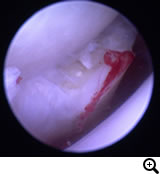

関節鏡検査

関節鏡視下で軟骨フラップを切除します。大型犬の成長期の跛行は消炎鎮痛剤等による対症療法ですませず、跛行原因の早期診断、早期治療が重要です。